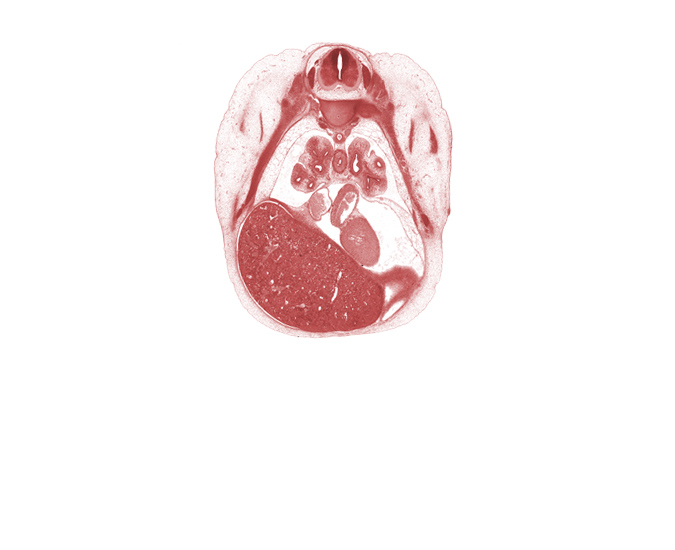

Carnegie Embryo #4430 | Location: 19-23

Keywords: T-5 intercostal nerve, T-5 spinal ganglion, central tendon of diaphragm, edge of diaphragm, head of rib 6, inferior vena cava, left atrium, left ventricle, lower lobe of left lung, lower lobe of right lung, lower secondary bronchus of left lung, lower secondary bronchus of right lung, medial tertiary bronchus of right lung, middle lobe of right lung, oblique fissure, rib 6, right postcardinal vein (azygos vein), subarachnoid space, sympathetic trunk

Source: The Virtual Human Embryo.